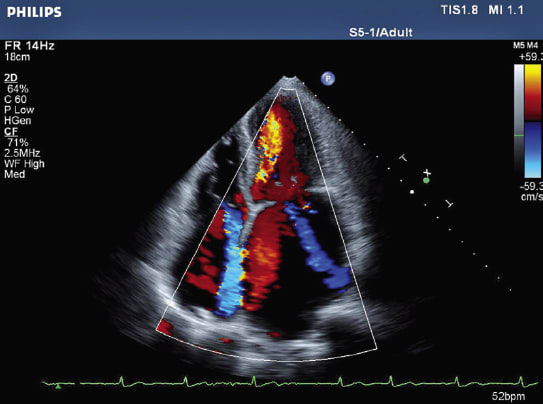

Other performance aspects are more critical. For one, vibration must be controlled to ensure patient stability. Motors and controllers that drive a patient table, for instance, must minimize vibrations that could make the patient uncomfortable and possibly upset sensitive organs. Likewise, motion control components regulating imaging systems must maintain stability, or images will be inaccurate. Galil Motion Control adapted its single-axis, DMC-1412 controller into an ultrasound system from Philips Medical Systems that can identify, for instance, distinct anatomic features of a developing infant. The controller incorporates a proportional-integral-derivative (PID) filter with acceleration and velocity feed-forward functionality for accurate control and smooth motion. The controller helps the ultrasound system probe with high accuracy and stability between frames, eliminating wobbly or bouncing images.